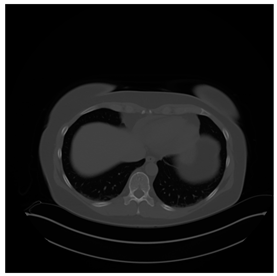

Breast-MRI-NACT-Pilot is an MRI-type image database, collecting breast medical images of 64 patients. Some samples are shown in Figure 12a.

Figure 12.

Sampled images in the tested benchmark databases: (a) Breast-MRI-NACT-Pilot (breast), (b) ACRIN-DSC-MR-Brain (brain), (c) NIH (chest), (d) Lung-PET-CT-Dx (lung), (e) Prostate-MRI (prostate), and (f) Other grayscale standard images.

ANIH is an X-ray type image database collecting chest medical images. Some samples are shown in Figure 12c.

Lung-PET-CT-Dx is a CT-type image database collecting lung medical images. Some samples are shown in Figure 12d.